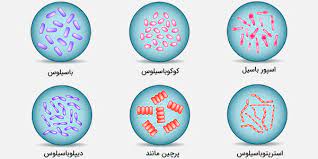

قیمت: 52٬000 تومان - دسته بندی فایل: پاورپوینتپاورپوینت رده بندی باکتریها

فروش ویژه پاورپوینت حرفه ای رده بندی باکتریها با تخفیف استثنایی فقط 55 هزار تومان تعداد اسلاید: 23 اسلاید